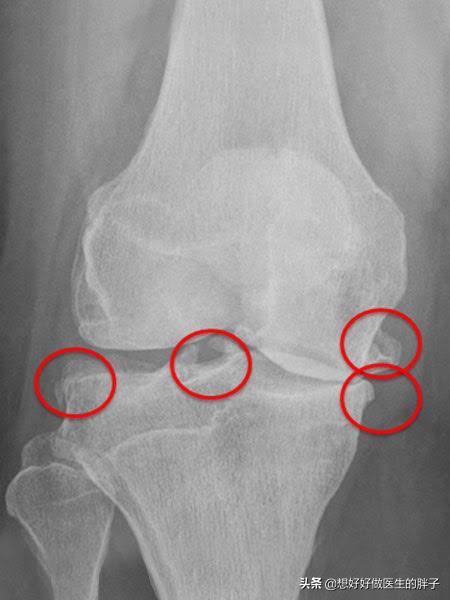

为什么有的人将骨赘称之为骨刺呢?就是因为有一些骨赘是突出骨骼范围之外的,其实这些骨赘比较小的时候,是不会对周边的软策划产生刺激和损伤的,但是如果当骨刺比较大以后,就有可能影响到周边的软策划、肌腱以及骨结构,从而产生疼痛、肿胀以及屈伸受限等症状。(下图的膝关节x线,患者就可能产生屈伸障碍、关节后方的疼痛或不适)

看到这里相信大家应该明白了,骨赘(骨刺、骨质增生)本来是帮忙的,之所以形成骨赘的基础是关节软骨的磨损,早期同时存在着纤维软骨修复、骨赘增生;晚期出现软骨的彻底破坏,表现为软骨硬化、软骨消失及软骨下局灶性骨坏死。晚期会导致严重的间隙狭窄和疼痛,需要手术解决大关节的问题。